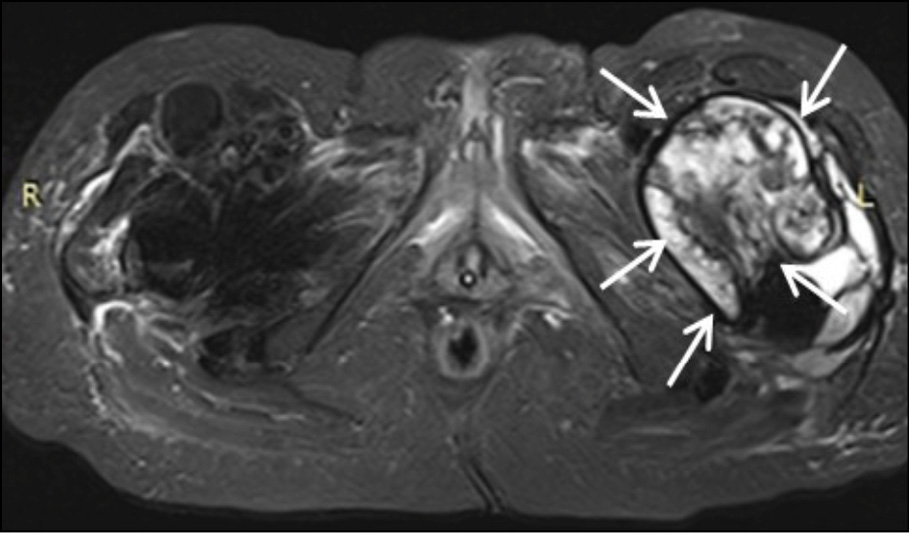

The chest X-ray was normal, with no hilar lymphadenopathy observed. Standard hip radiography was satisfactory and did not show any obvious alterations around the implant (Figure 1). The patient’s white blood cell count was 17.2×109/L with a neutrophilia (14.2 × 109/l), C-reactive protein (CRP) of 20mg/l (<0.5 mg/l), thrombocytopenia, elevated fibrinogen (478 mg/dl), and elevated high-sensitive troponin (1893 ng/dl), which was attributed to Type II ischemia, which further refers to a form of ischemia associated conditions that cause an imbalance between myocardial oxygen supply and demand. The patient was initially administered piperacillin - tazobactam and daptomycin intravenously (i.v). Due to persistent pain which extended above the knee the next days, the patient underwent Magnetic Resonance Imaging (MRI) (Figure 2a-e). MRI showed large encapsulated multilobular fluid collection with internal septa adjacent to the endoprosthesis of the left hip joint (Figure 2a-2b). This collection extended anteriorly beneath the deep fascia, causing displacement of the quadriceps muscle and protruding into the iliopsoas pouch. Its maximum outer diameter measured 12 cm.

Figure 2a - Axial STIR image at the level of femoral neck. Large encapsulated multilobular fluid collection with internal septa is observed adjacent to the endoprosthesis of the left hip joint (white arrows).

Figure 2b - Coronal STIR image at the level of pubic bone. Large encapsulated multilobular fluid collection with internal septa is depicted adjacent to the endoprosthesis of the left hip joint (white arrows).